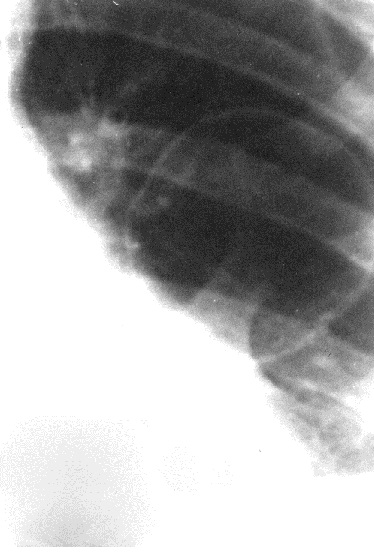

Морфологическим субстратом кольцевидной тени является полость, причем кольцевидная тень отображает стенку этой полости. Полость может содержать жидкость. В этом случае нижняя часть полости имеет затемнение с верхней горизонтальной границей – горизонтальный уровень жидкости под газом (рис. 9).

Рис. 9. Рентгенограммы органов грудной полости в прямой (а) и правой боковой (б) проекциях. Справа в нижней доле – большая кольцевидная тень с толстой стенкой и горизонтальным уровнем жидкости – абсцесс.